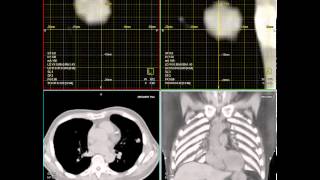

4D Xray reconstruction using SIRT video

MR Lumbar Plexus - CISS Technique @ 3T Moving lung tumor during imaging (radiation therapy)